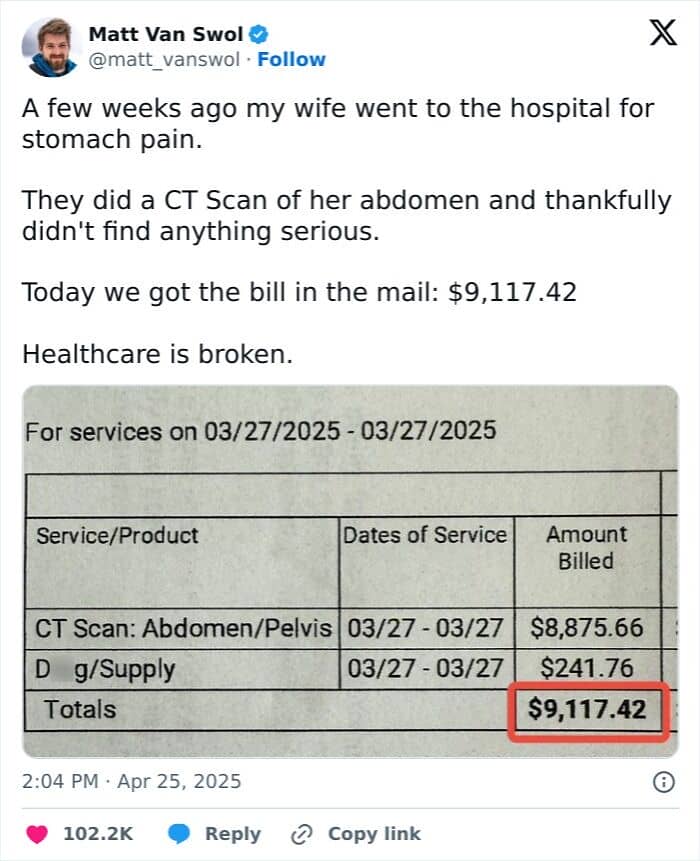

#27 Bill For A Stomachache